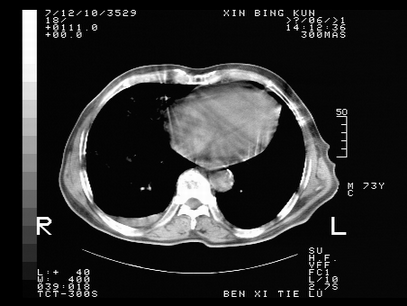

标题: CT10820:男,73岁,病史肺TB,现病史肺炎,直肠CA术后 [打印本页]

标题: CT10820:男,73岁,病史肺TB,现病史肺炎,直肠CA术后

1.两肺结核.2.两肺多发转移瘤.3右侧少量胸腔积液4.主动脉钙化.

双肺多发结节及条片状致密影,右侧少量胸腔积液。临床:直肠ca术后,肺tb病史。综合考虑:1 双肺转移!2 继发性肺结核合并感染!

此人病史较复杂,原有肺结核,直肠癌术后。肺部病灶形态亦呈多形性。因此,不可仅以一种病来解释肺部的病变。双肺多发的类圆形结节灶,结合病史还是首先考虑转移瘤,而双肺其余病灶还需结合化验室检查,结核或肺部感染在无其它检查资料的情况下不好排除。还是那句话----放射科医生不是开照像馆的,我们也是医生,看片一定要多结合临床及其它检查资料。要当一名合格的放射科医生,并不比当一名临床医生容易,我们可别把自已不当医生看。

左肺上叶下叶背段,右肺中下叶见多发斑片状、条索状高密度影,兵变周围小结节影形成“树芽”样改变。 左肺上叶舌段近前胸壁处及右肺中叶内侧段见结节影。右侧胸膜腔内见液体密度区。纵隔内未见明确增大淋巴结。考虑左肺上叶舌段近前胸壁处及右肺中叶转移瘤可能性大。两肺继发型肺结核。右侧胸腔积液。

还有心包少量积液。